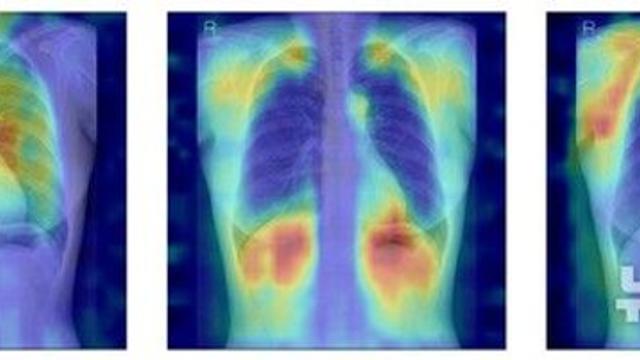

thumbimg

"흉부 엑스레이로 골다공증 여부 판단"…'AI 모델' 개발

모두서치 2025.11.28

사진 = 뉴시스   서울대병원이 흉부 X선만으로 정상·골감소증·골다공증을 분류하는 인공지능